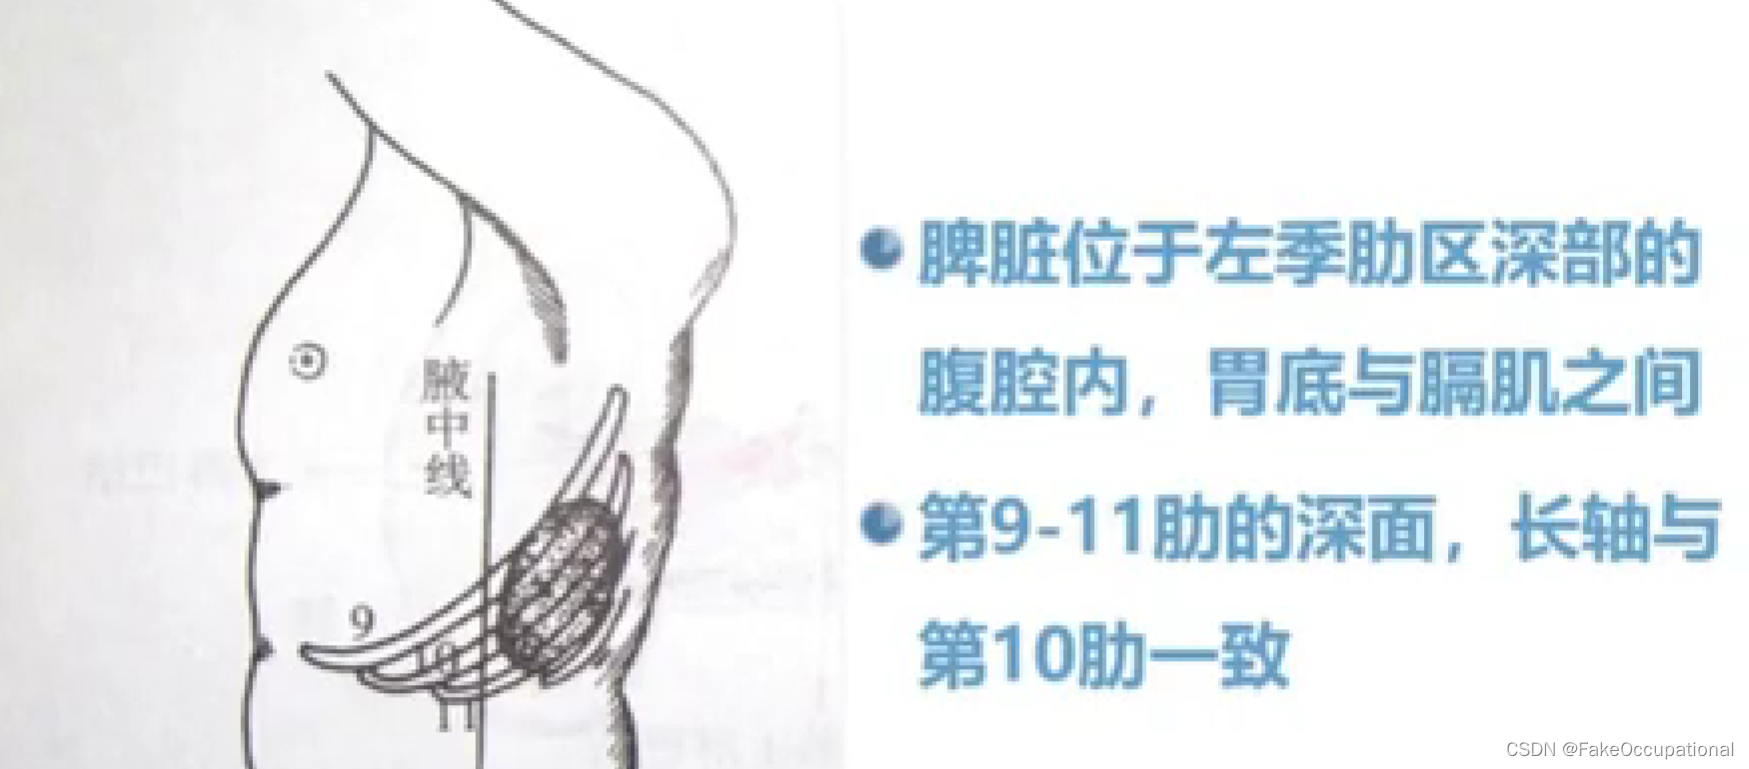

脾脏解剖及正常声像图